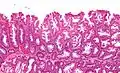

La partie profonde des glandes est souvent élargie, a tendance à se diviser en deux ou trois branches et à s’horizontaliser, c'est-à-dire à se disposer parallèlement à la musculaire muqueuse et non pas perpendiculairement à elle, comme dans les polypes hyperplasiques conventionnels et les adénomes festonnés traditionnels.